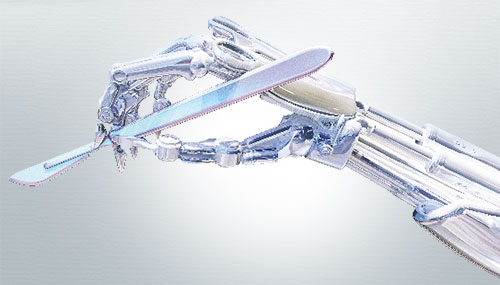

We at NHS OrthoRobotics, are committed to provide safety. COVID-19 has changed the way we manage our everyday lives, but it has not eliminated. We need to seek precautions and health care treatment.

When there is a breakdown of the cushioned covering of the bones end (cartilage) and the natural joint becomes so bad that it affects your daily routine due to pain & disability, simple options like lifecycle modification ,medicines, exercises, physiotherapy stop working, it is time to consider joint replacement surgery.